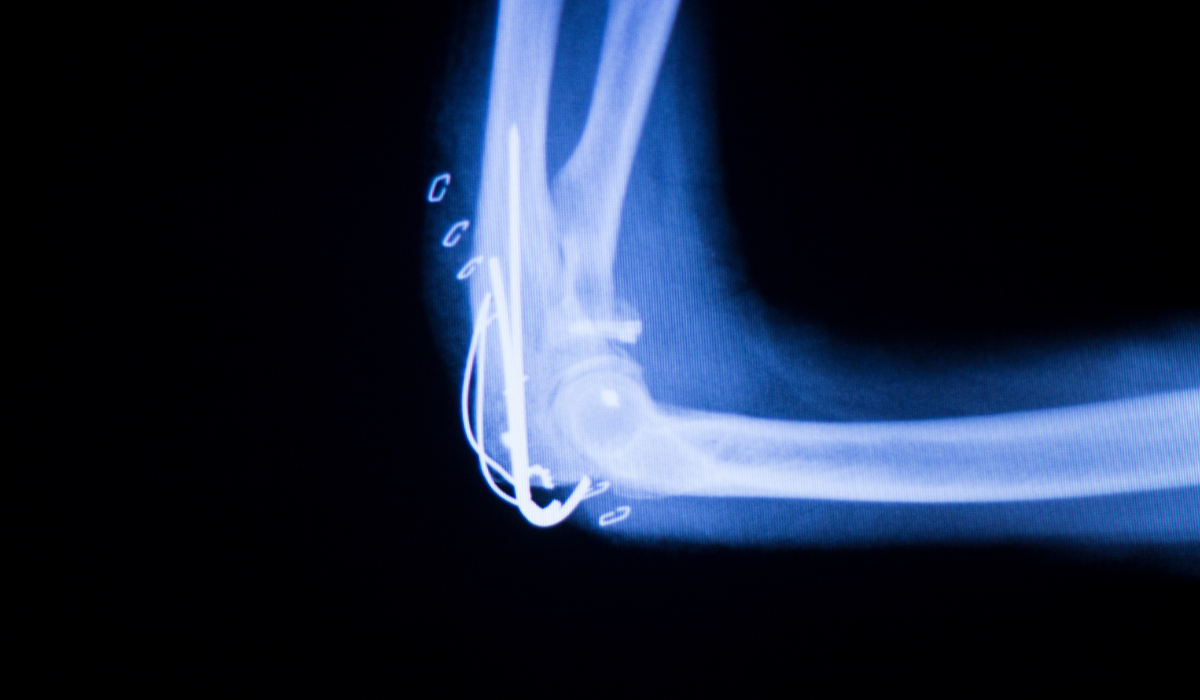

The elbow joint is a complex hinge joint formed where three bones meet: the humerus (upper arm bone), the radius, and the ulna (both forearm bones). This joint allows for two types of movement — flexion and extension (bending and straightening) as well as rotation of the forearm. Stabilized by muscles, tendons, ligaments, and cartilage, the elbow plays a crucial role in everyday tasks like lifting, throwing, and rotating the arm.

Our orthopedic team provides a comprehensive range of elbow-related services, from accurate diagnosis to advanced surgical interventions. Whether you are dealing with repetitive strain injuries, elbow fractures, ligament tears, or joint degeneration, our clinic is equipped to offer personalized treatment plans that meet your needs. We prioritize minimally invasive techniques like arthroscopy to minimize pain and reduce recovery time.